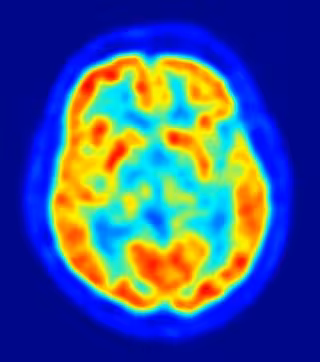

Neurocientíficos de la Universidad de Nueva York han identificado las partes del cerebro que utilizamos para recordar la sucesión de eventos dentro de un episodio. El estudio, que aparece en el último número de la revista 'Science', mejora nuestra comprensión de cómo se procesan los recuerdos y ofrece una guía básica para hacer frente a potenciales trastornos relacionados con la memoria.

Investigaciones anteriores han demostrado que el lóbulo temporal medio del cerebro (MTL) tiene un papel importante en la memoria declarativa, es decir, la memoria de hechos o sucesos, y que los daños en esta área causan un deterioro de la memoria. Más específicamente, la memoria declarativa se encuentra alterada en los pacientes que sufren Alzheimer. Sin embargo, poco se sabe acerca de cómo las estructuras individuales dentro de la MTL recuerdan información sobre cuándo ocurrió un suceso específico, como, por ejemplo, el orden de los brindis en una boda.

Los investigadores de la Universidad de Nueva York, el científico Yuji Naya y la profesora Wendy Suzuki, ambos del Center for Neural Science, centraron su estudio en el MTL. Para realizar el estudio, los investigadores hicieron pasar a un grupo de sujetos animales a través de una tarea de memoria de orden temporal en la que se presentó una secuencia de dos objetos visuales y los sujetos tenían que recuperar la misma secuencia después de un retraso. Con el fin de realizar la tarea correctamente, los sujetos necesitaban recordar tanto los elementos individuales visuales ("qué") como el orden temporal ("cuándo"). Durante el experimento, los investigadores monitorearon la actividad de las células cerebrales individuales en el MTL.

Sus resultados mostraron que dos áreas principales del MTL están involucradas en la integración de "qué" y "cuándo": el hipocampo y la corteza perirrinal. El hipocampo, conocido por tener un papel importante en una variedad de tareas de la memoria, proporciona una señal de sincronización incremental entre los eventos clave, proporcionando información sobre el paso del tiempo desde el último evento, así como del tiempo estimado hasta el próximo. La corteza perirrinal integra la información sobre "qué" y "cuándo", qué ocurrió primero o segundo en una serie.